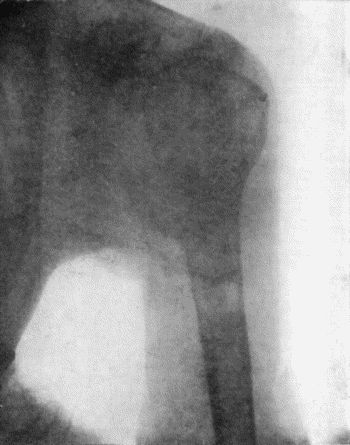

137.Radiogram of Upper End of Femur in Osteomyelitis Fibrosa 478

138.Radiogram of Right Knee showing Multiple Exostoses 482